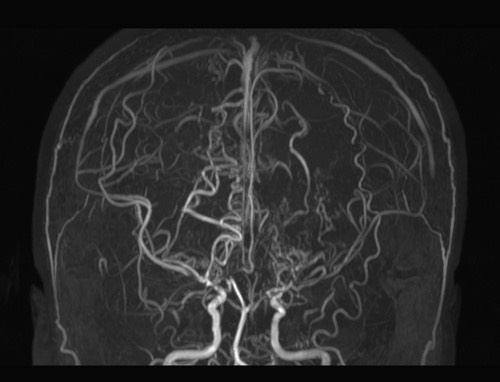

모야모야병은 뇌기저부의 주요 혈관이 서서히 협착되고 막히면서 뇌혈류가 감소하는 만성 진행성 뇌혈관 질환입니다. 협착이 진행된 부위를 대신해 뇌는 생존을 위해 얇고 약한 혈관망을 만들어 혈류를 보충하려 하고, 이 새로운 혈관들이 촬영 영상에서 연기처럼 퍼져 보인다고 하여 ‘모야모야’라는 이름이 붙었습니다. 기전적으로는 내경동맥 말단부와 중대뇌동맥·전대뇌동맥의 기시부에 병변이 가장 잘 생기며, 시간이 지남에 따라 양쪽에 대칭적으로 나타나는 특징을 보였습니다. 이 질환은 단순한 혈관 협착이 아니라 진행성 변화이기 때문에 치료하지 않으면 혈류 부족이 심해지고 뇌 손상이 누적될 수 있습니다. 또한 뇌기능이 체력·호흡·체온 변화 등에 민감하게 반응하기 때문에 과호흡, 울음, 격렬한 운동, 감염 등으로 증상이 악화될 수 있습니다. 즉, 모야모야병은 시간이 지나면서 뇌혈류를 감소시키고 뇌졸중 위험을 높이는 질환이며, 평생 관리가 필요한 만성적 특성을 갖고 있습니다.

따라서 가족력이 있거나 의심되는 증상이 있다면 뇌 MRA·MRI 등의 정기검진이 도움이 되며, 조기 진단 시 치료 효과도 훨씬 높아집니다.